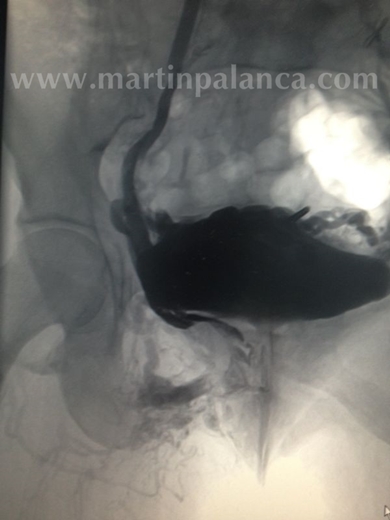

4º)